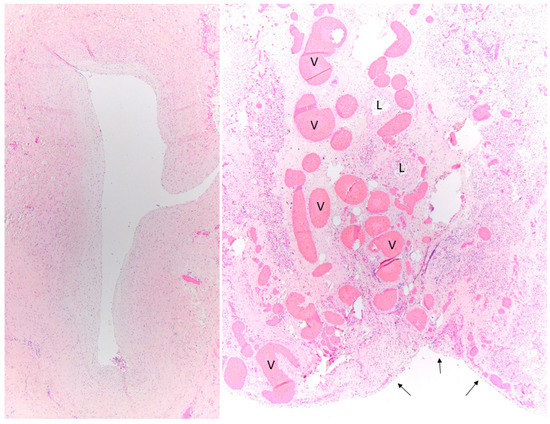

- Kovach, A.E.; Magcalas, P.M.; Ireland, C.; McEnany, K.; Oliveira, A.M.; Kieran, M.W.; Baird, C.W.; Jenkins, K.; Vargas, S.O. Paucicellular fibrointimal proliferation characterizes pediatric pulmonary vein stenosis: Clinicopathologic analysis of 213 samples from 97 patients. Am. J. Surg. Pathol. 2017, 41, 1198–1204. [Google Scholar] [CrossRef]

- Pogoriler, J.E.; Kulik, T.J.; Casey, A.M.; Baird, C.W.; Mullen, M.P.; Jenkins, K.J.; Vargas, S.O. Lung Pathology in Pediatric Pulmonary Vein Stenosis. Pediatr. Dev. Pathol. 2016, 19, 219–229. [Google Scholar] [CrossRef]